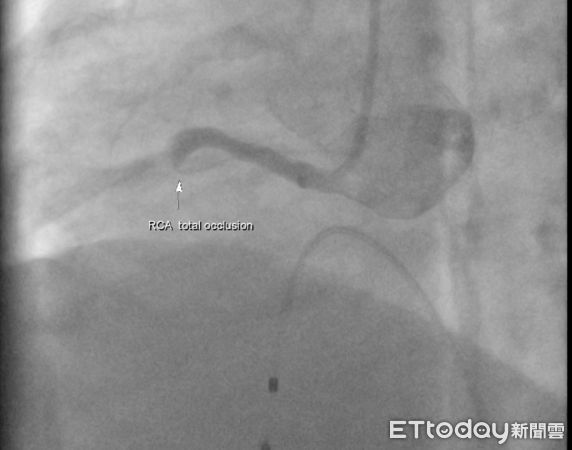

▲貨車司機心肌梗塞還硬上路飆100多公里回台中就醫,醫生搖頭。(圖/院方提供)

▲李男本身就有心血管病史,當時急性心肌梗塞發作,還一路從桃園撐到台中。(圖/院方提供)